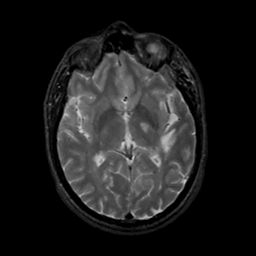

MR Study #14, June 2, 1991 -- Slice #25